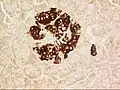

- Mouse islet immunostained for pancreatic polypeptide

- Mouse islet immunostained for insulin

- Mouse islet immunostained for glucagon